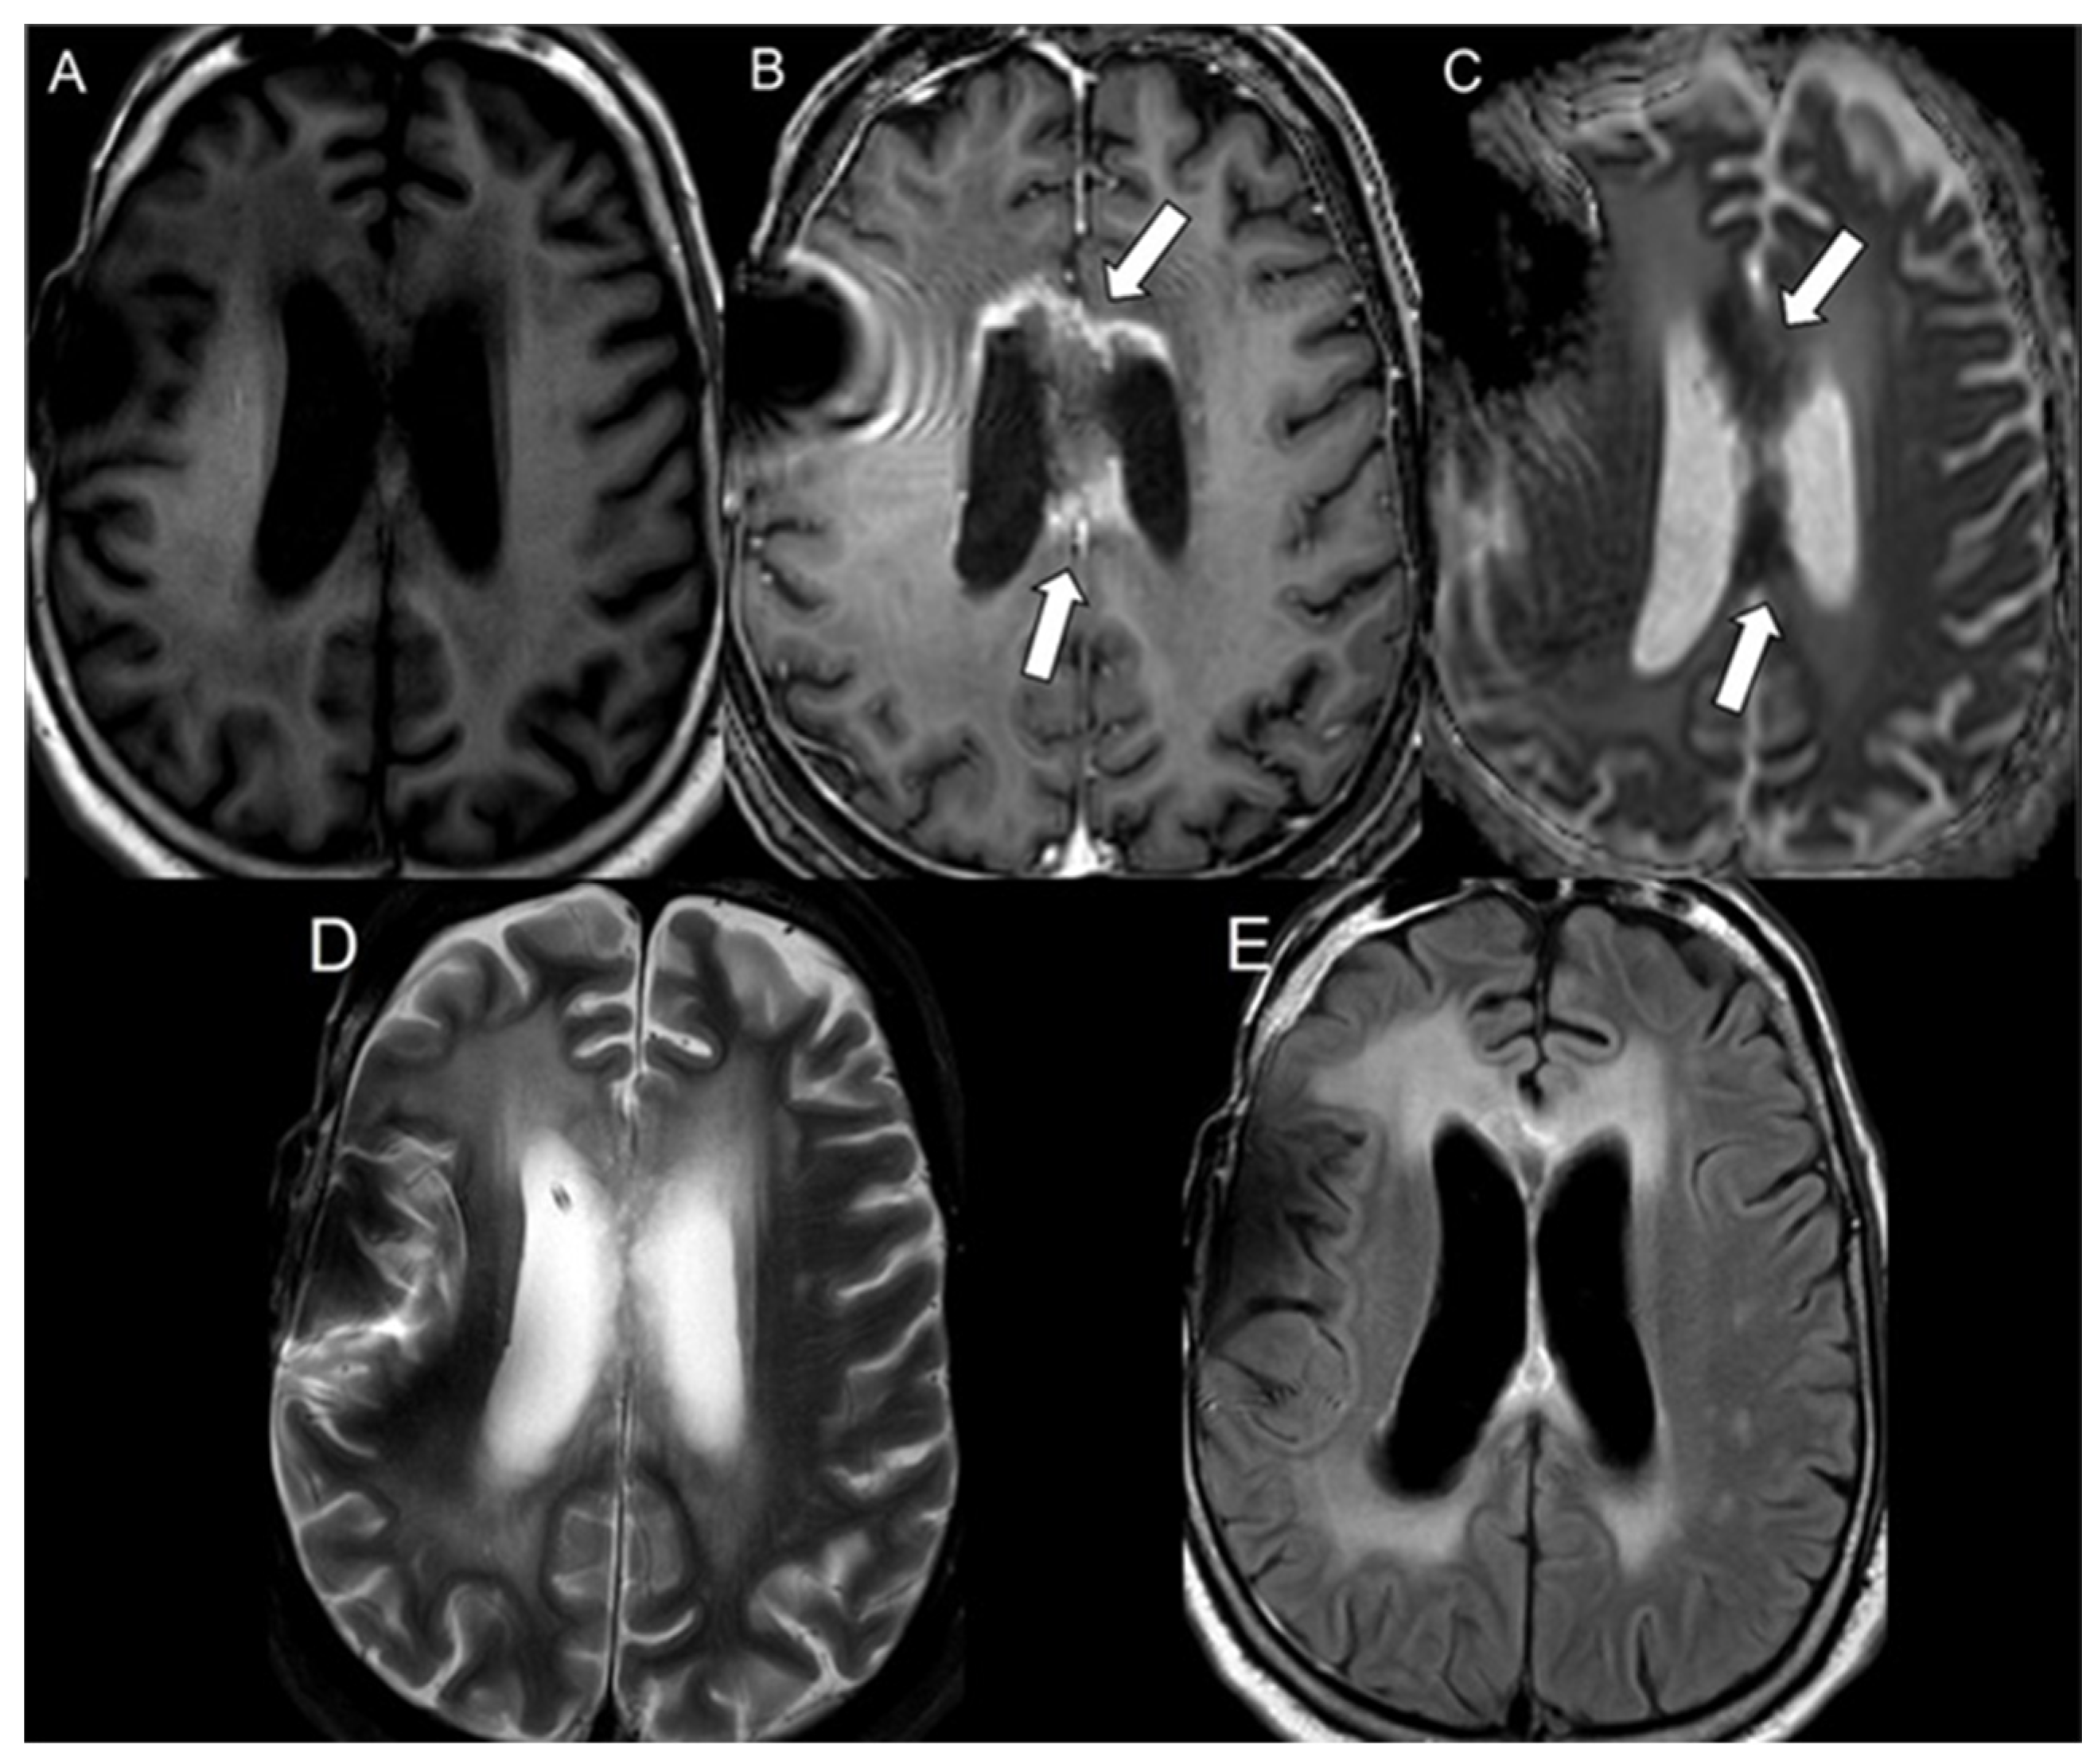

| Progressive glioblastoma | 49 | 752.8 ± 132.5 | 709.2 ± 63.5 | 0.08 |

| Progressive glioblastoma | 0.59 | 0.41–0.70 |

| Progressive glioblastoma | 49 | 1.07 ± 0.22 |